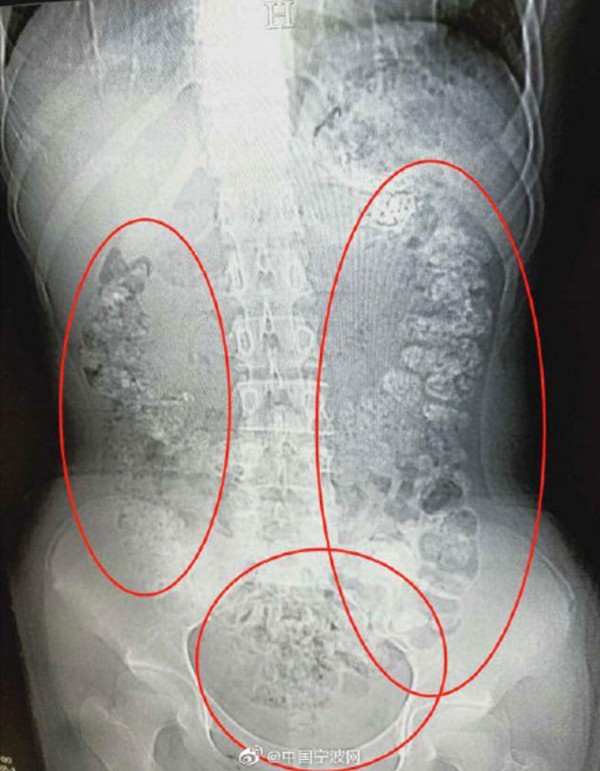

Có rất nhiều quả bóng hình cầu nhỏ chen chúc bất thường trong bụng bé gái 14 tuổi. Bác sĩ kết luận đây chính là các hạt trân châu trong trà sữa - một loại đồ uống đang rất được giới trẻ yêu thích.

Ảnh chụp cho thấy có rất nhiều hạt trân châu bị kẹt trong bụng bệnh nhi

Bác sĩ cũng phải hốt hoảng khi nhìn kết quả chụp chiếu thấy hàng trăm hạt trân châu trong bụng bé gái 14 tuổi mê trà sữa.